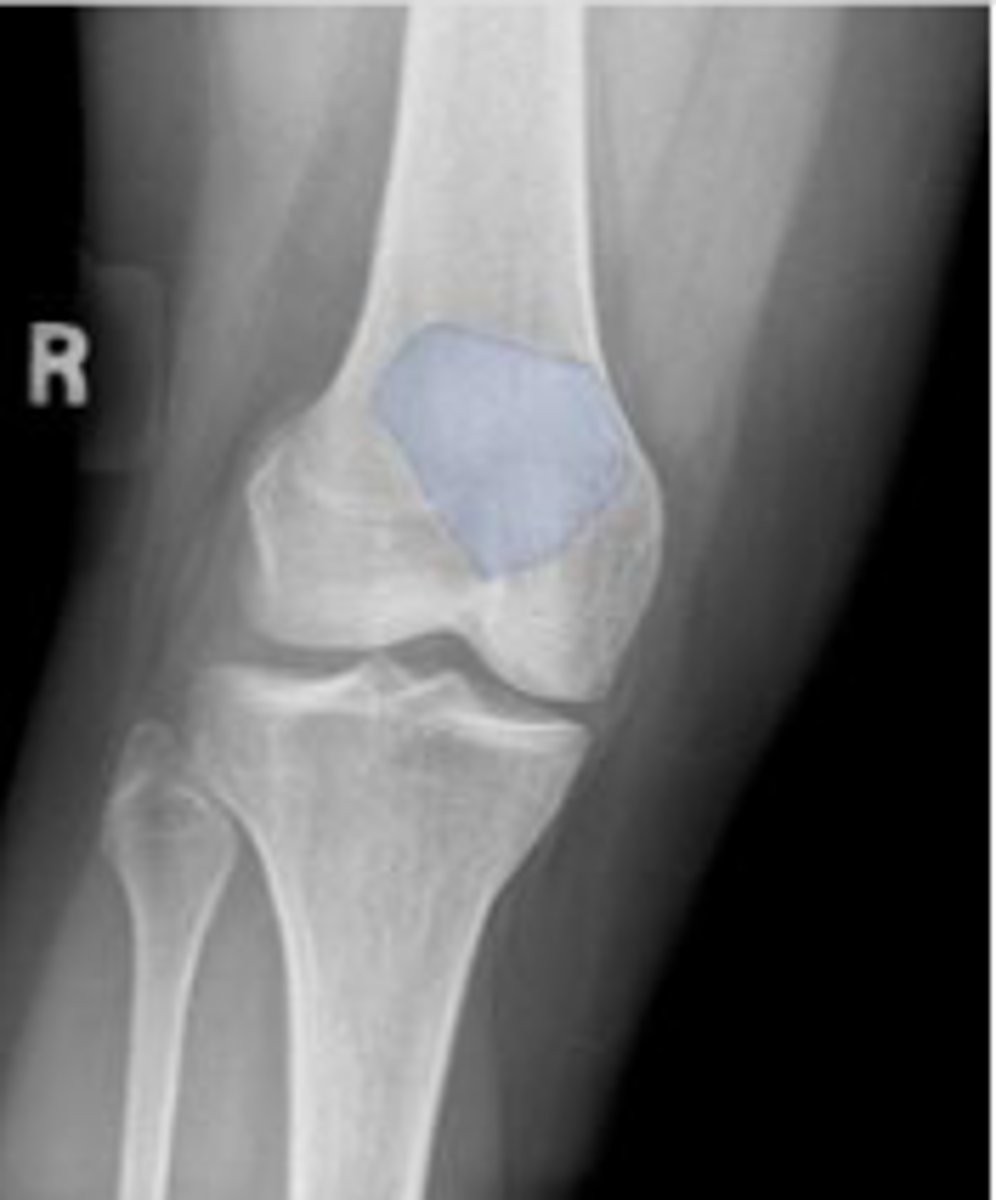

Right internal oblique knee

What is the name of the radiographic view?

Right patella

What is outlined?